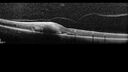

69 year old female with vision loss for a few months in the right eye. Images show a macroaneurysm in the right eye. The lesion had bled and FA showed no leakage. No treatment was done. VA improved from 20/40 - 20/32